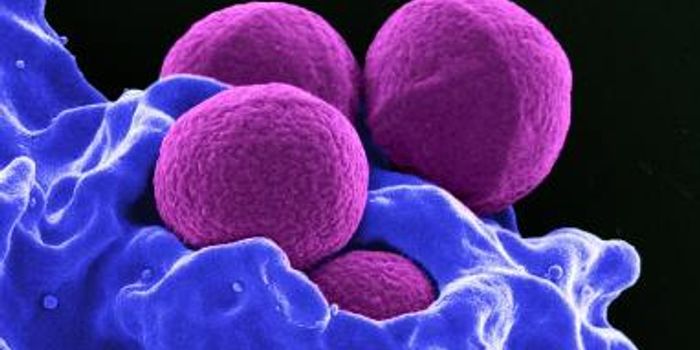

MAR 18, 2016ImmunologyHow are macrophage immune cells activated during an inflammatory response when pathogens invade? Scientists thought they ...